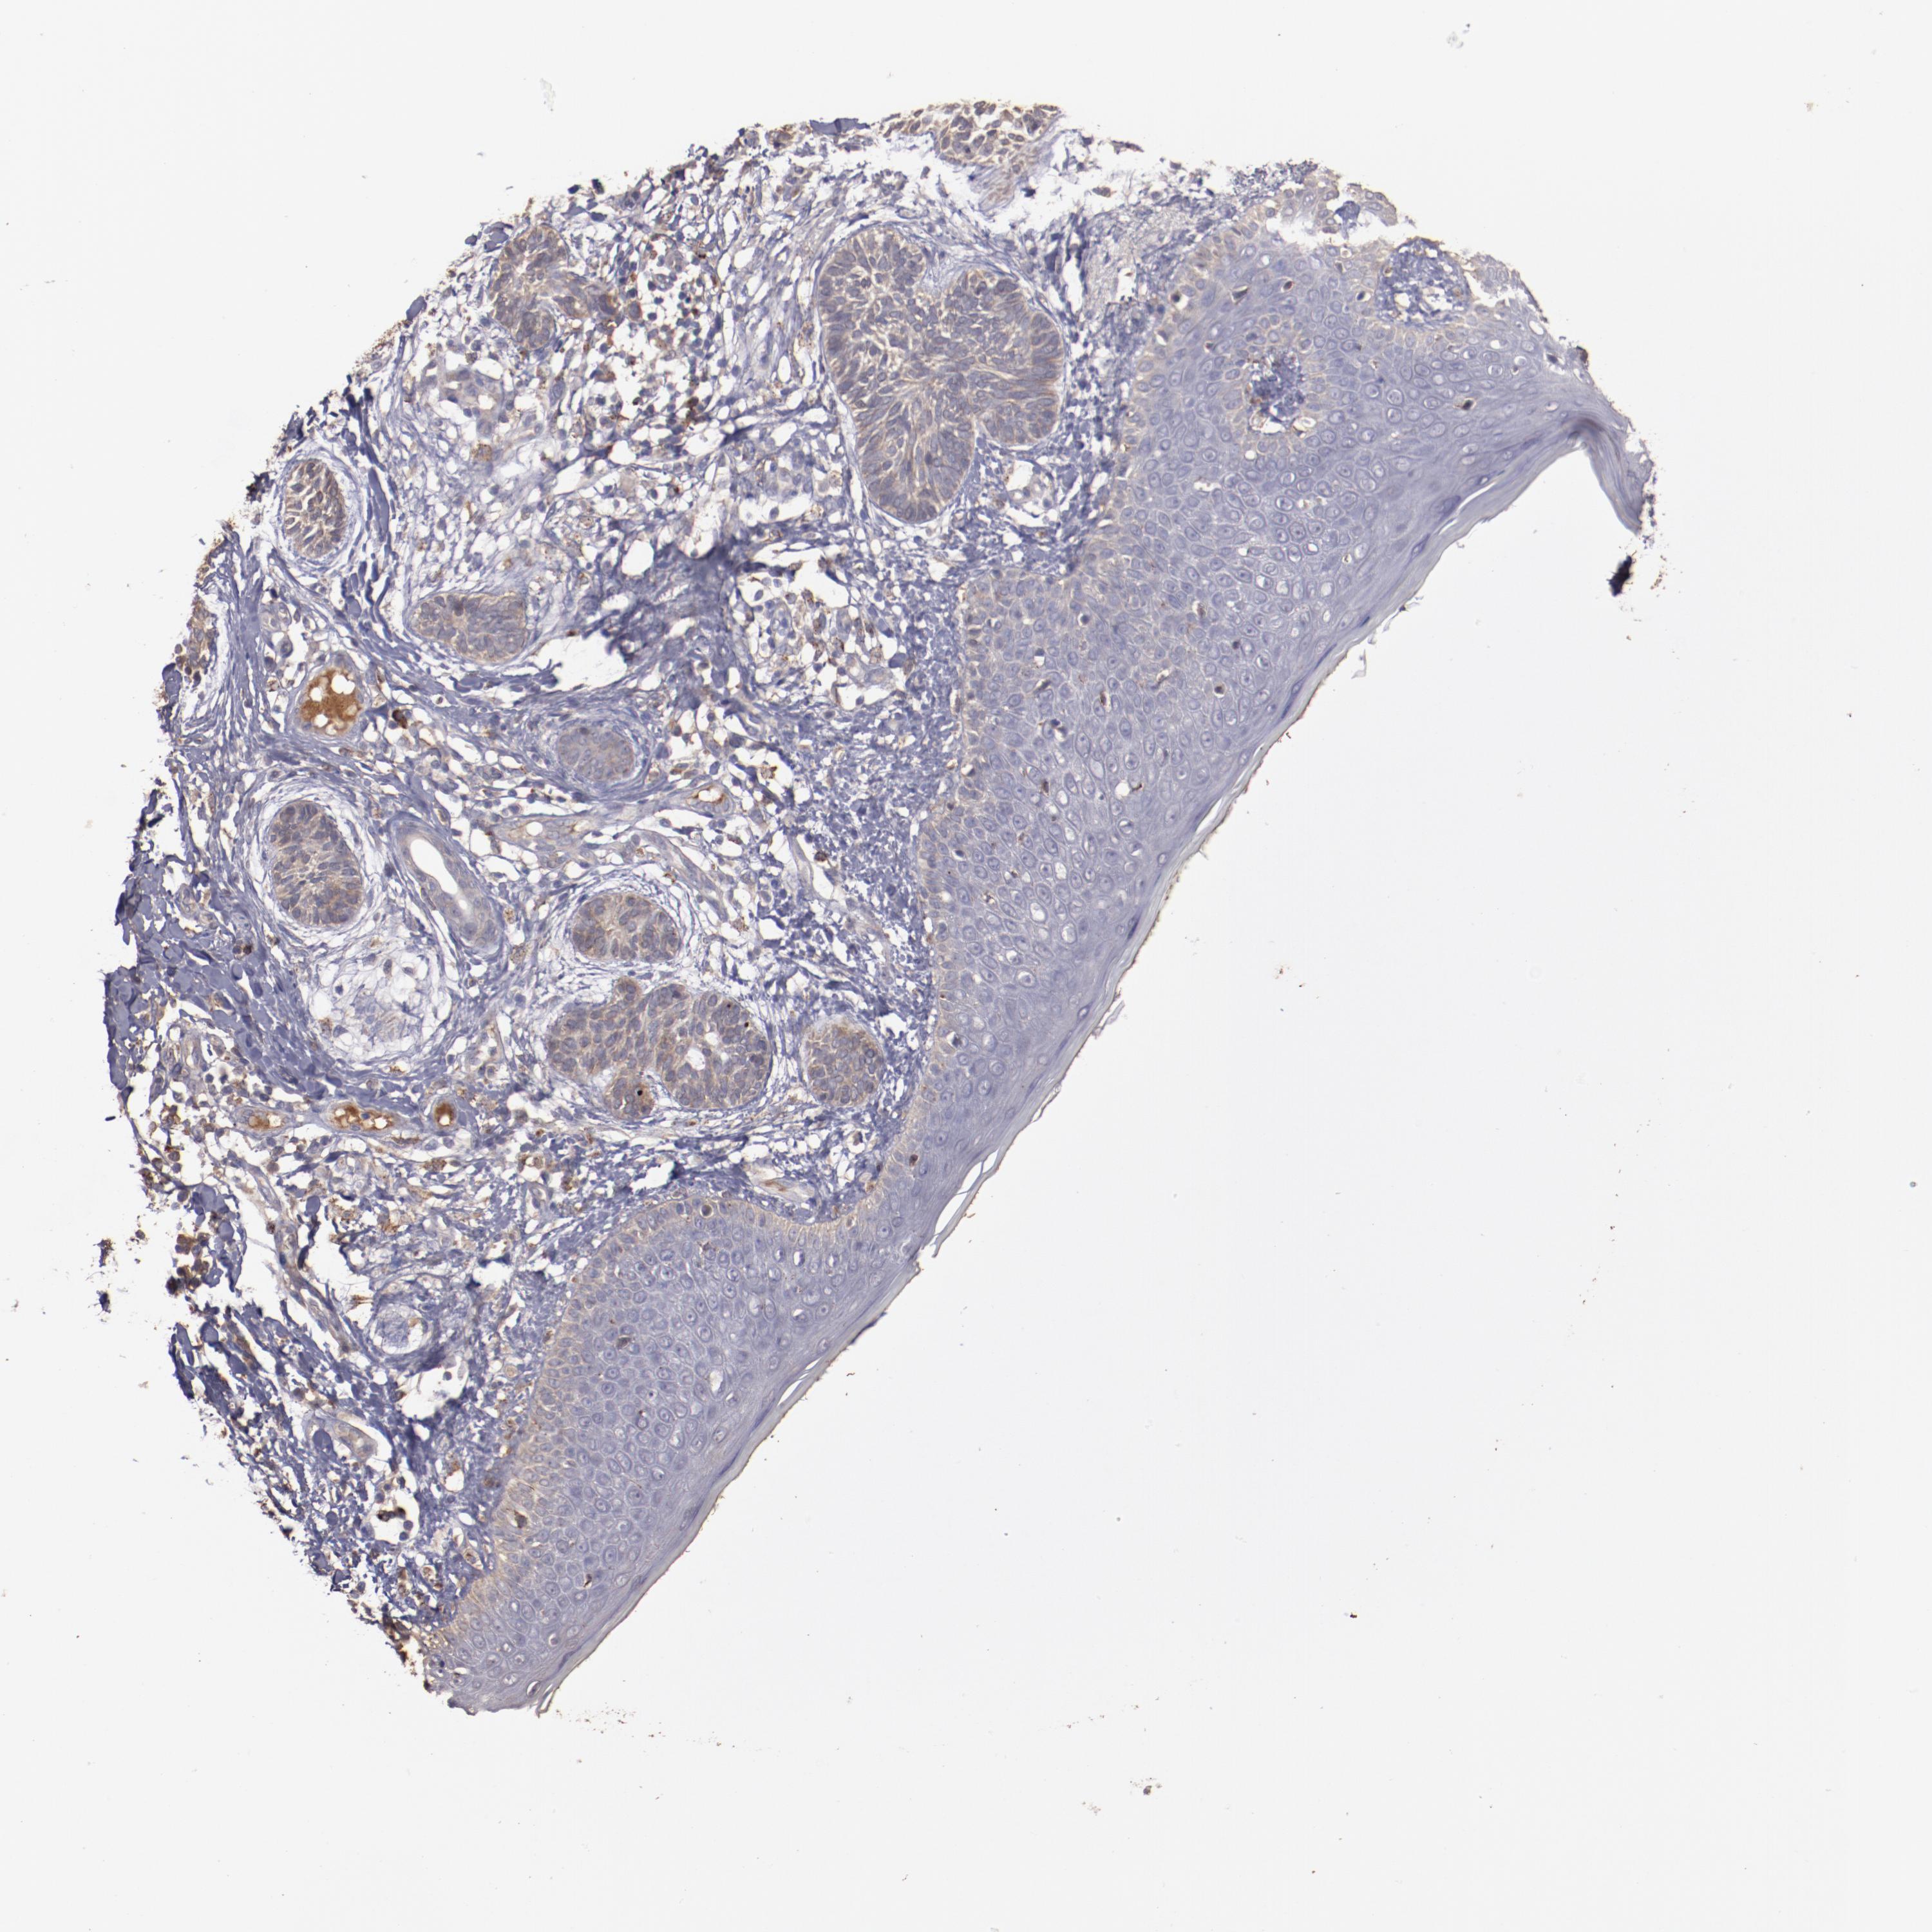

SKIN CANCER - Protein expressioni

A mouse-over function shows sample information and annotation data. Click on an image to view it in a full screen mode. Samples can be filtered based on level of antibody staining by selecting one or several of the following categories: high, medium, low and not detected. The assay and annotation is described here.

Each image is clickable and will lead to virtual microscopy that enables deeper exploration of all samples and also displays staining intensity scores, fraction scores and subcellular localization as well as patient and tissue information for each sample.

Antibody HPA002945

Staining

High

Medium

Low

Not detected

Intensity

Strong

Moderate

Weak

Negative

Quantity

>75%

75%-25%

<25%

None

Location

Nuclear

Cytoplasmic/membranous

Cytoplasmic/membranous,nuclear

Squamous cell carcinoma, NOS

Basal cell carcinoma